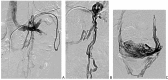

Nutcracker syndrome in adolescent with perineal pain: An interesting case of an adolescent with perineal pain due to pelvic congestion from nutcracker syndrome with relief after balloon venoplasty and sclerotherapy

Nutcracker phenomenon is the descriptor for a patient's anatomy whenever the left renal vein becomes compressed between the abdominal aorta and the superior mesenteric artery. Nutcracker syndrome is the terminology used when the nutcracker phenomenon is accompanied by symptoms including pain (abdominal, flank, pelvic), hematuria, and orthostatic proteinuria. Diagnosis can be made with Doppler ultrasound, venography, computed tomography, or magnetic resonance imaging. This case demonstrates some of the typical findings of nutcracker syndrome. The limited clinical features and interesting imaging findings, in addition to the young age of the patient, make this a notable case.